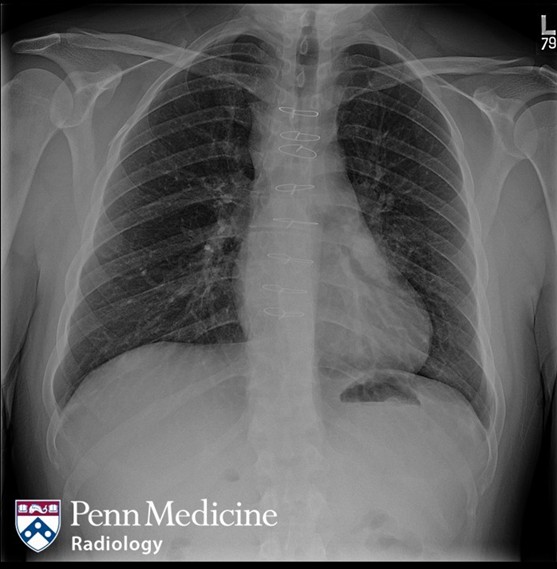

Cases of the Week

Check out our Cases of the Week!